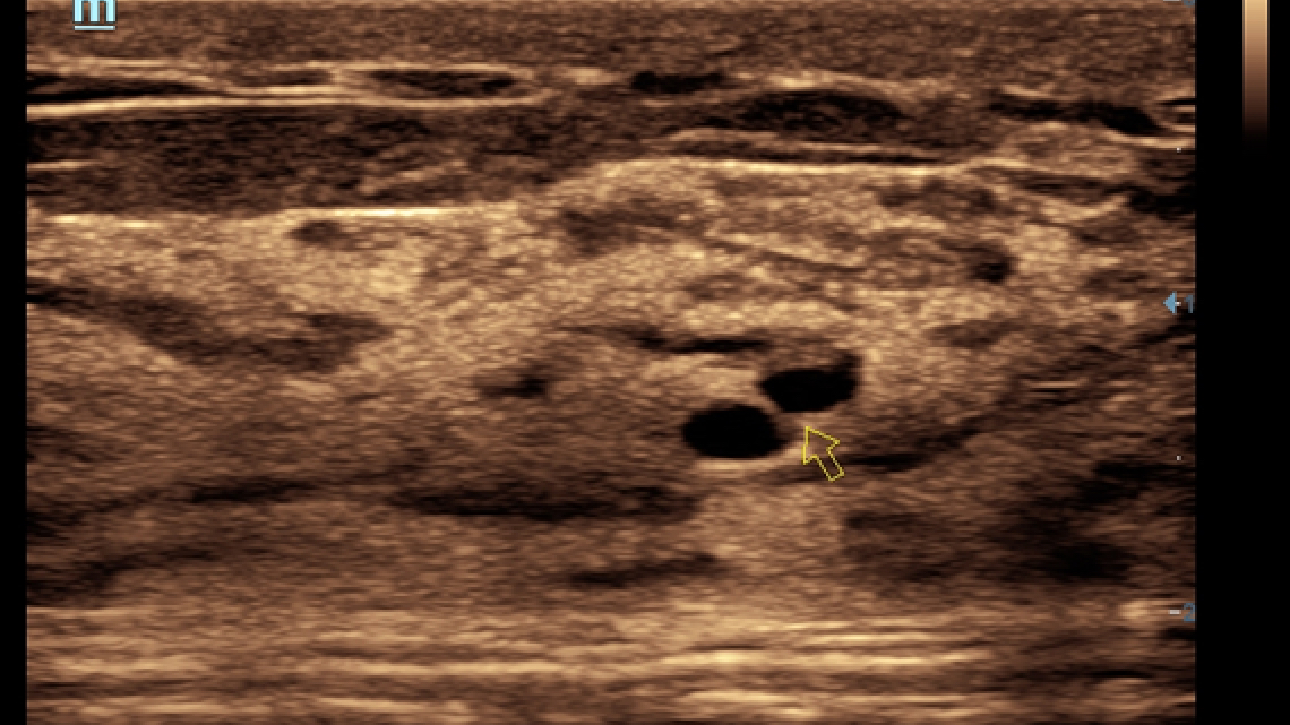

X-Insight is een inzichtelijke oplossing om meer visie te krijgen.

De gloednieuwe oplossing van Mindray is het geslaagde product dat is voortgekomen uit voortdurende klantinzichten in klinische behoeften in combinatie met steeds evoluerende, geavanceerde ultrasoundtechnologie?n. Vol energie en gebrand op toekomstgerichte inzichten en eindeloze mogelijkheden: dankzij de verhoogde schaalbaarheid wordt de oplossing continu verbeterd.

Als allround partner zet DC-60 Exp met X-Insight zich in om een allesomvattende oplossing te zoeken waarmee u alle aspecten van uw dagelijkse klinische activiteiten gemakkelijk en trefzeker kunt beheren.

De DC-60 Exp met X-Insight is ontworpen op basis van diepgaand inzicht in klantbehoeften om hoge effici?ntie met nauwkeurige beeldverwerking te leveren, dankzij eXacte helderheid, eXceptionele intelligentie en eXcellente ervaring.